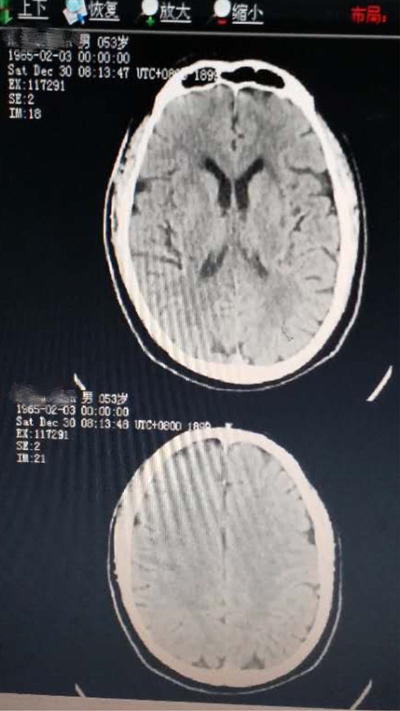

病例三:第二例脑梗死行阿替普酶溶栓治疗

患者彭某某,女,74岁,新市镇新书村人,因突起言语不清伴意识障碍2小时,于2018年2月3日入院,有高血压、冠心病史且姐妹有中风病史,留有后遗症。体查:嗜睡,言语含糊,体查欠配合,口角不斜,伸舌不能,四肢肌力3级,左侧巴氏症可疑,右侧正常,考虑急性脑梗死可能性大。

溶栓前头颅CT,排除脑出血

患者无静脉溶栓禁忌症,告知家属患者病情危重,溶栓风险大,可能效果欠佳,家属积极配合同意溶栓,立即启动阿替普酶静脉溶栓,约一天半左右神志转清,语言清晰,肢体肌力正常。

第二天复查头颅核磁未见明显异常